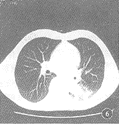

18例CT图像显示病灶呈明确的软组织块影,12例瘤体内有小空洞(图5),空洞内CT值为气体密度,8例在肿块的周围有炎性渗出(图6),4例瘤体边缘呈分叶状(图7),7例在肿块边缘具有长毛刺影(图8),9例在假瘤的附近可见局限性胸膜增厚,形成幕状,线状粘连带。

图5 CT扫描见左下肺肿块内多个小空洞影

CT图像把假瘤与肺的境界面显示得非常清楚,即使胸片表现为大片状或团块状模糊影,但在CT图像上则表现为境界清楚的块影[3]。本组30例胸部平片仅1例发现空洞,而18例CT扫描就有12例显示小空洞存在,这种小空洞可以单发,也可以多发。除此以外,CT图像上显示肿块周围长毛刺,胸膜增厚,粘连征像对本病诊断有着重要意义[3~7]。